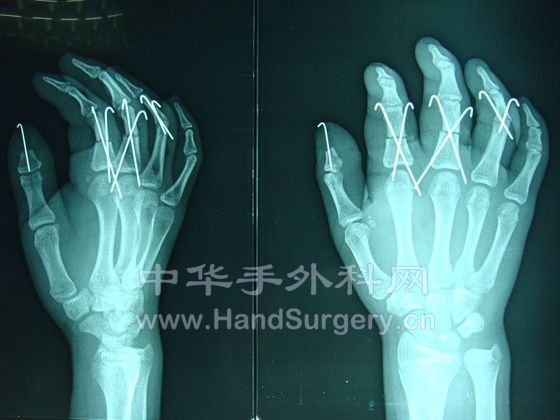

一个断掌+5个断指,显示我科实力!

我这里有术后半年的手术图片,发上来给大家看看,我们曾作出了手外科功能最好的多指离断!